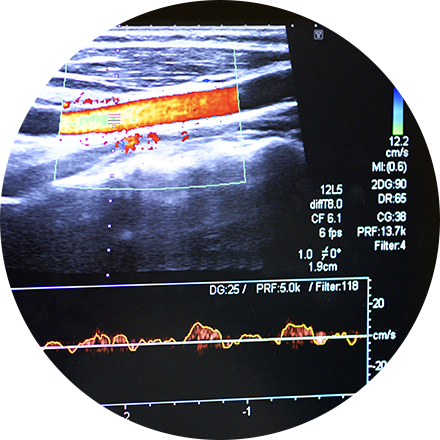

Carotid Ultrasound

Carotid ultrasound uses sound waves to produce pictures of the carotid arteries in the neck which carry blood from the heart to the brain. A Doppler ultrasound study, a technique that evaluates blood flow through a blood vessel, is usually a part of this exam. It is most frequently used to screen patients for blockage or narrowing of the carotid arteries which may increase the risk of stroke.